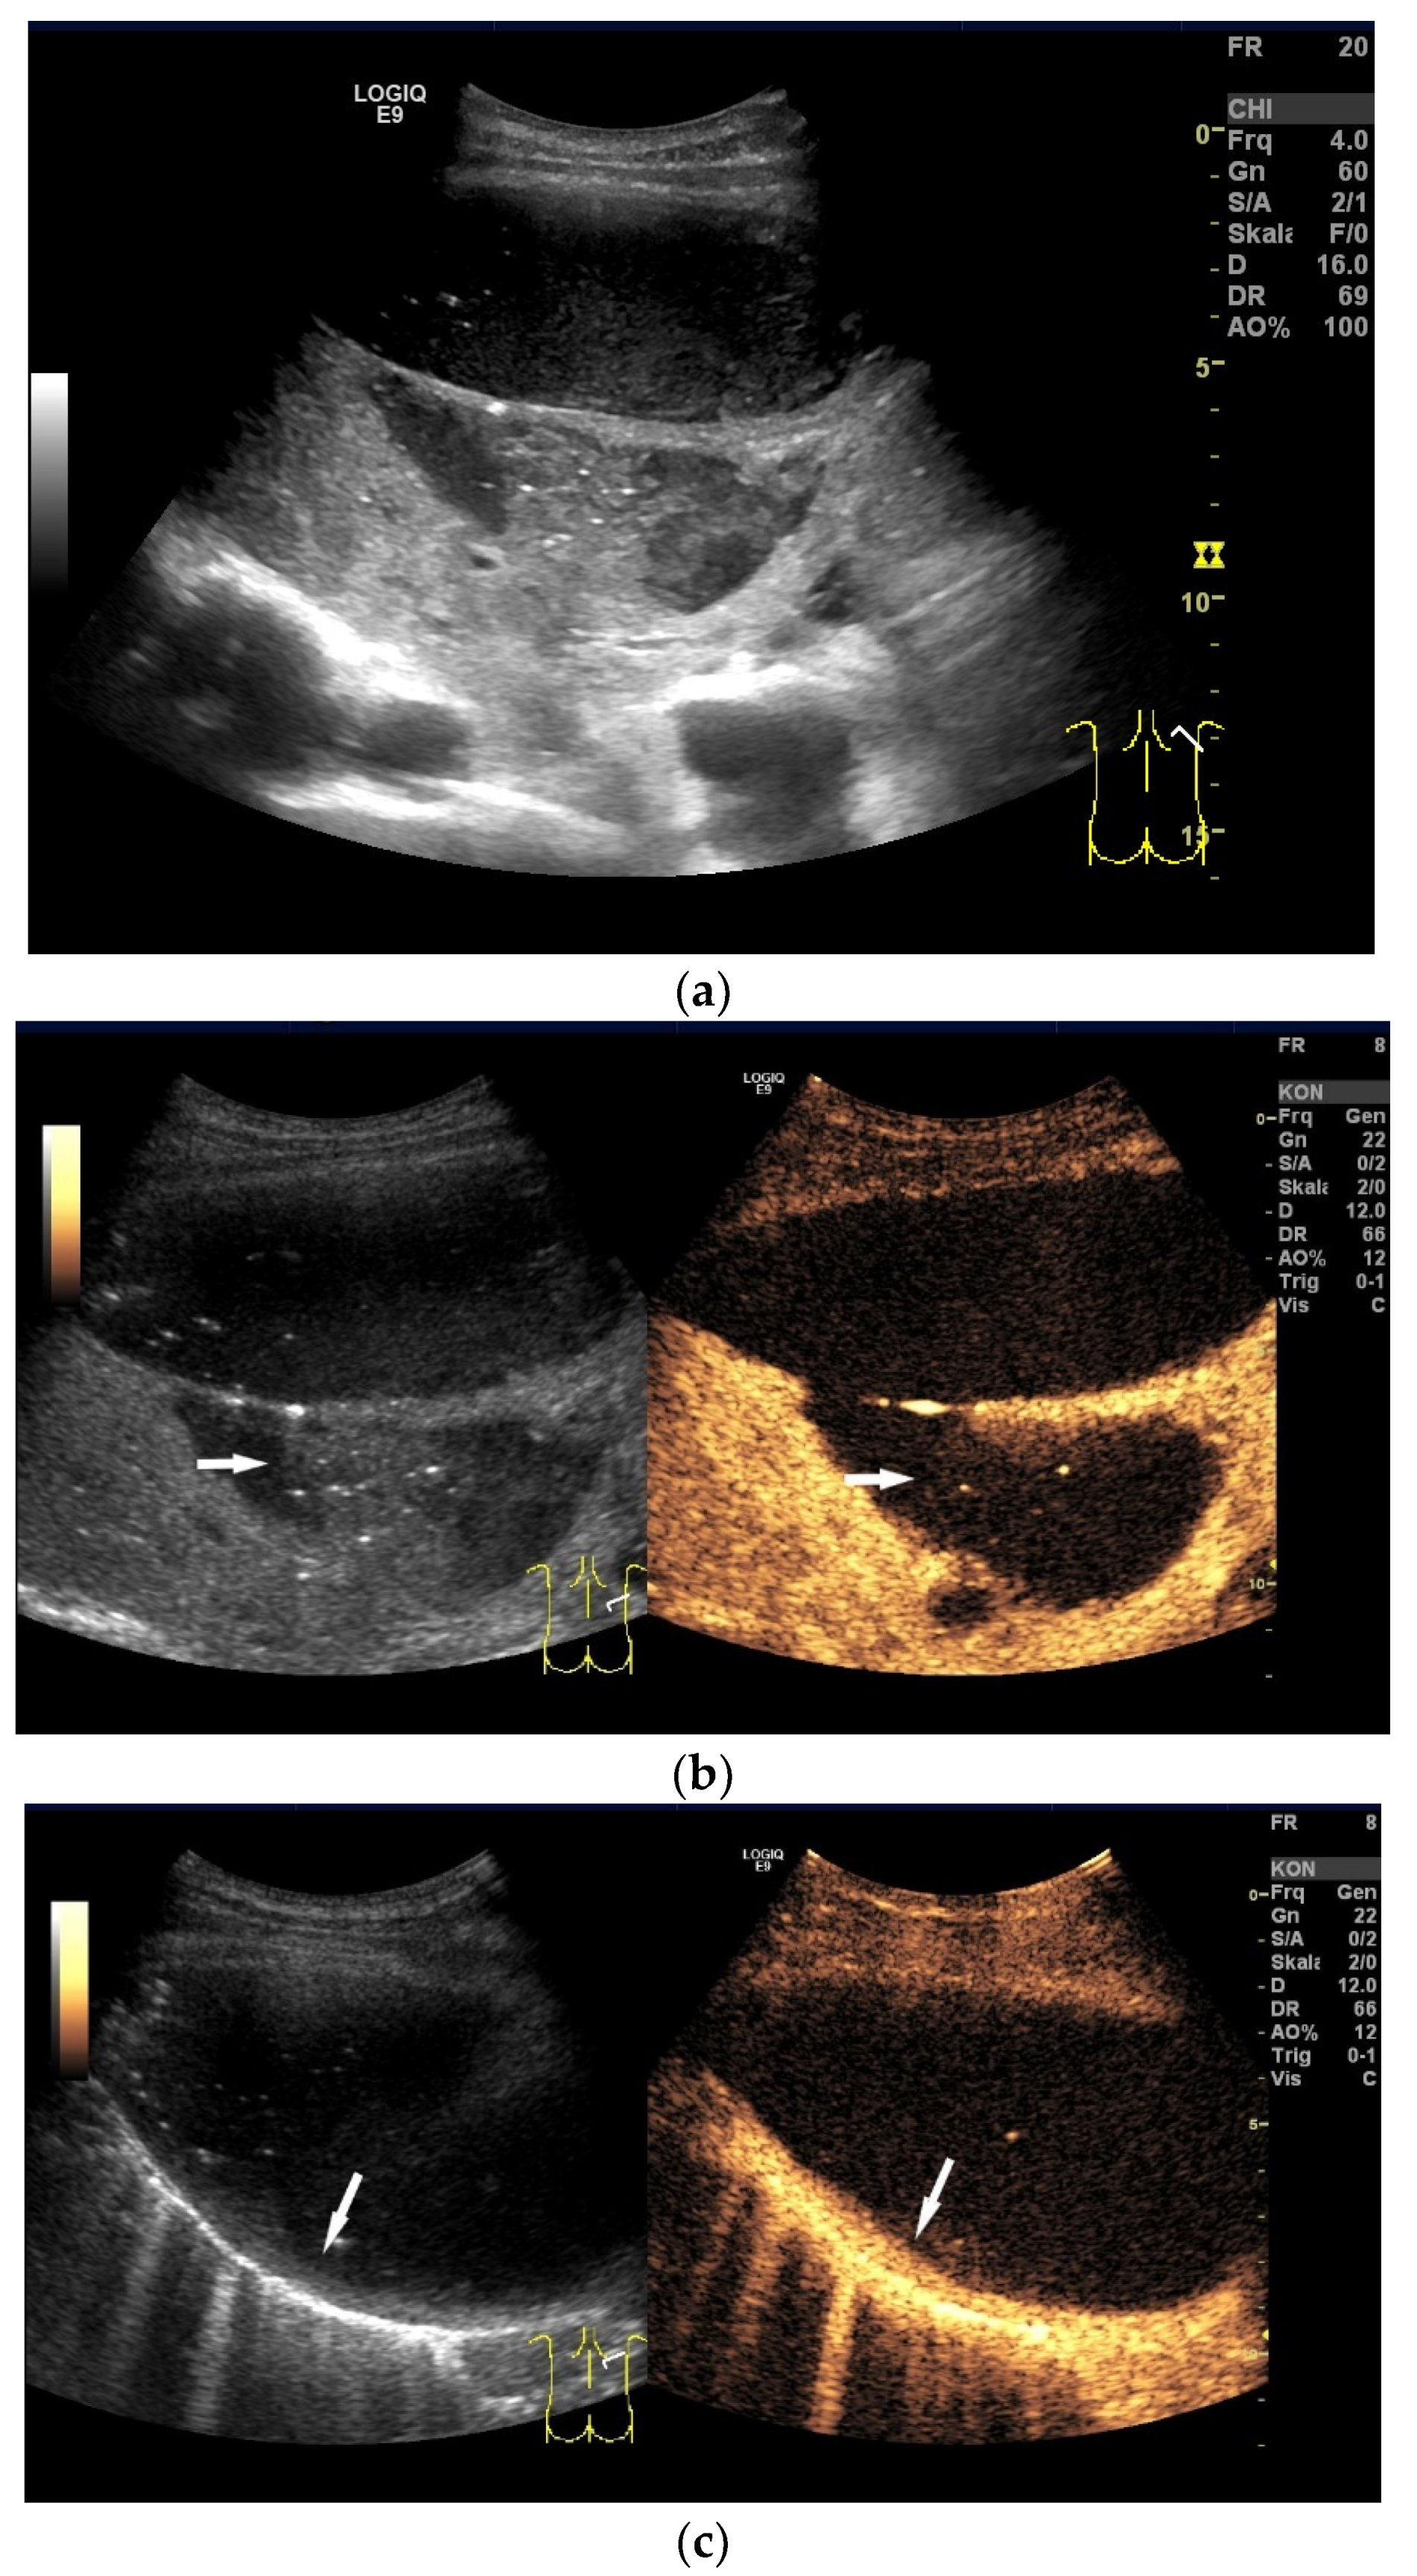

| Tuberculous pleuritis | Pleura effusion with fibrin strands, pleural calcification, and thickening. Hypoechoic granulomatous inflammation and granulomas with hyper-enhancement on CEUS in thickened pleura. Hypoechoic caseous abscesses in thickened pleura, hypo- or nonenhanced, heterogeneously enhanced lesions, with contrast-enhanced septations and contrast-enhanced rim. |